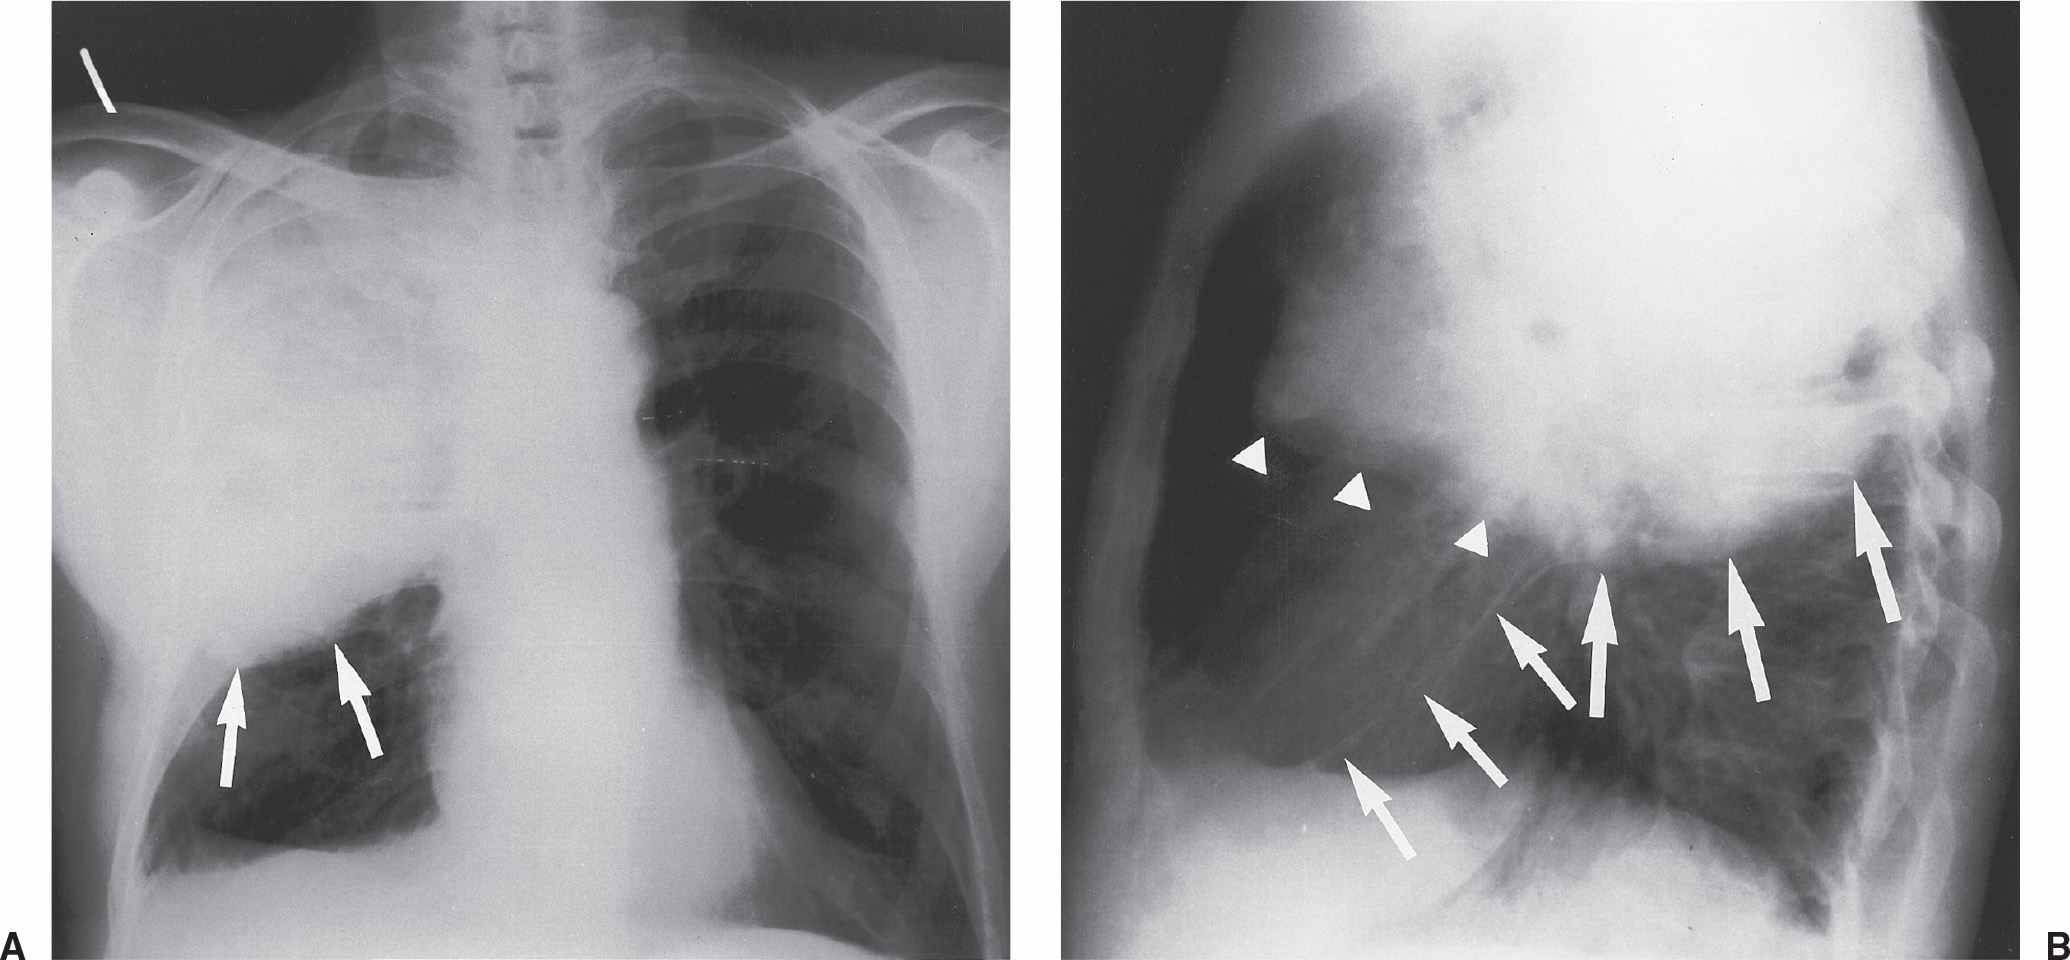

Web pulmonary hodgkin's lymphoma presenting with a bulging fissure sign intern med. Blow up (as in explosion) burst (as in to explode) example sentence. The fissure sign appears as a linear area of decreased radioactivity on a perfusion scan which corresponds in position and. There are a variety of signs that are used in sign language to express anger or frustration. Web bulging right horizontal fissure with right upper lobe consolidation and air bronchograms. Web occasionally cases may give a bulging fissure sign. Caused by a variety of diseases and. Pa (a) and lateral (b) radiographs of the chest show dense consolidation of the right middle lobe secondary to klebsiella pneumoniae. Web this sign is used to say (sign synonyms) blast. Web bulging fissure sign a term of art referring to the loss of the relative linearity of the lung fissures as seen on a plain film, which is characteristic of exudative pneumonia—e.g.,. Web pulmonary hodgkin's lymphoma presenting with a bulging fissure sign intern med.